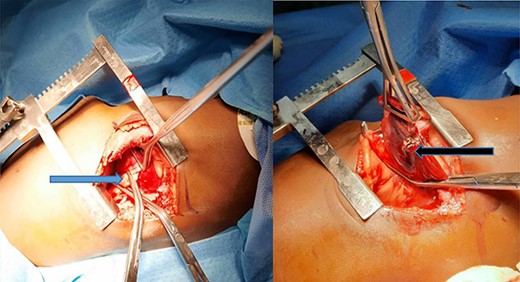

At surgery, the aberrant artery from the descending thoracic aorta (Fig. 3A) was dissected, isolated and doubly ligated with silk 1 and clips. A wedged resection of the sequestrated lung (Fig. 3B) was done, with Fig. 4 showing the normal lung after resection. No gastrointestinal tract communication was identified. A size 18F chest tube was left in situ after hemostasis. Patient was extubated on table and spent 2 days in the intensive care unit before being step down to the ward. The chest tube was removed on post-operative day 2 and he was discharged home on post-operative day 4 with subsequent follow-up on out-patient basis. He has been well with no complaints 6 months after surgery. Histopathologic evaluation of the resected sequestrated lung reported of thick-walled blood vessels in the lung parenchyma as well as evidence of hemorrhage and chronic inflammation within the alveolar spaces consistent with intralobar pulmonary sequestration.

The normal lung after anomalous artery ligation and wedge resection of the sequestrated lung.